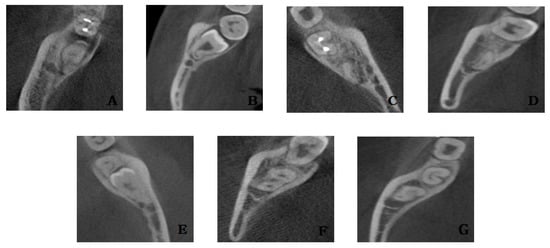

2.3. CBCT Analysis

The positional relationship between the root of the mandibular third molar and the inferior alveolar nerve was analyzed. In the panoramic radiograph, the root of the mandibular third molar and the inferior alveolar nerve overlapped, but CBCT was observed to see if they were actually in contact with each other, and whether they were on the buccal side, on the lingual side, below the root, or between the root if not on the bucco–lingual side (Figure 5). In addition, the relationship between the root of the mandibular third molar and the lingual cortical bone was also observed. If continuity of the lingual cortical bone was lost due to the root, it was classified as cortical bone perforation. Finally, patients who complained of nerve injury after surgical extraction were investigated using medical records.

Figure 5. Relationship between the inferior alveolar canal and roots in cone beam computer tomography views: (A) root darkening in panoramic view, (B) root deflection in panoramic view, (C) root narrowing in panoramic view, (D) dark line in apex in panoramic view, (E) loss of white line in panoramic view, (F) inferior alveolar nerve (IAN) narrowing in panoramic view, and (G) IAN diversion in panoramic view.